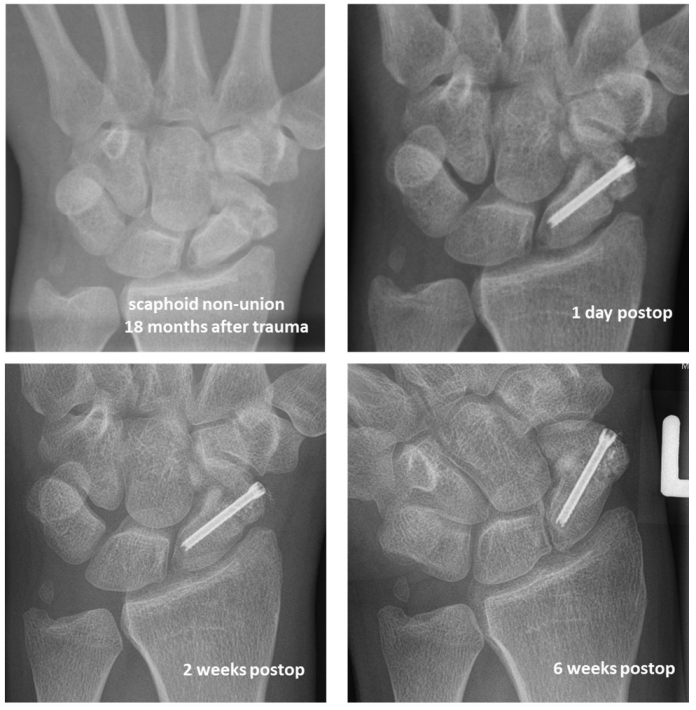

Figure 3 [Fig. 3] shows an X-ray follow-up of an 18 months old scaphoid non-union successfully treated with a bone graft from the iliac crest and an HCS (Synthes®).

Figure 3: X-ray of an 18 months old scaphoid non-union of a 32 y.o. male treated with a bone graft from the iliac crest and an HCS (Synthes®), 6 week post-operative follow-up